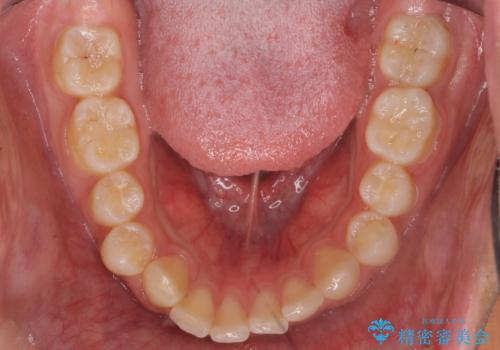

出っ歯が気になる 歯をぬかずに治療

- 前歯が出ているのを気にして来院。

左のかみ合わせが1本分ずれていましたが、機能的には問題ないのでそのまま変えずに治療しています。

ずれている分を、上の歯を1本抜くか(ワイヤー矯正になります)、右上の奥歯を1本分後ろに送るか、そのまま前歯を並べるのかを選んでいただきました。

右のかみ合わせをそのままに、最小限の動かし方で見た目を改善しました。